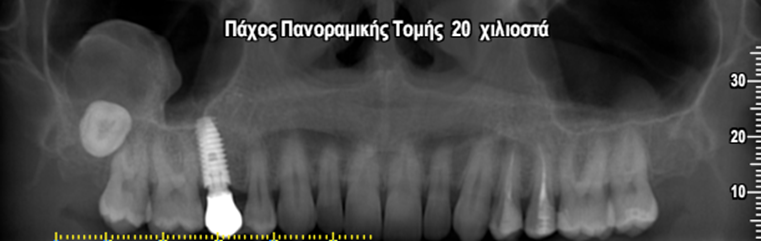

Περίπτωση εκτεταμένης οδοντοφόρου κύστης σχετιζόμενης με τον έγκλειστο 3ο γομφίο 18 όπου παρατηρείται εμπλοκή του δεξιού ιγμορείου άντρου σε γυναίκα ασθενή ηλικίας 45 ετών.

Η κύστη έχει προκαλέσει ιδιαίτερα εκτεταμένη υπέγερση του εδάφους του ιγμορείου άντρου προβάλλοντας εντός αυτού και καταλαμβάνοντας μεγάλο τμήμα της αεροφόρου του κοιλότητας.

Παρατηρείται επίσης λέπτυνση και ήπια έκπτυξη του πλαγίου τοιχώματος του ιγμορείου άντρου.